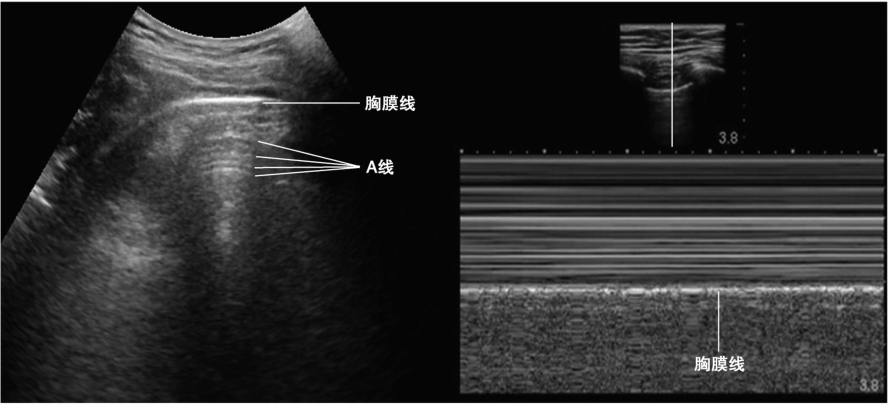

超声声束在正常含气肺组织表面发生强散射。肺部病变的情况下(肺组织的气液比例发生变化),会形成特征性的超声伪像,肺部超声正是主要基于这些在肺组织病理情况下对新出现的超声伪像进行诊断(图2)。

正常肺组织超声图像显示清晰的胸膜线、A线及胸膜滑动征,M型超声提示胸膜线以下区域呈均匀的“海岸征”

(1)胸膜线

正常情况下呈线状强回声,因为脏壁两层胸膜正常情况下紧邻,这条亮线反映的实际是胸壁软组织与肺组织之间的界面。

(2)A线

与胸膜线平行的数条高回声伪影,属于混响伪像。提示肺内含有气体。

(3)胸膜滑动征

脏壁两层胸膜在呼吸过程中相对移动,在M型超声上表现为“海岸征”。